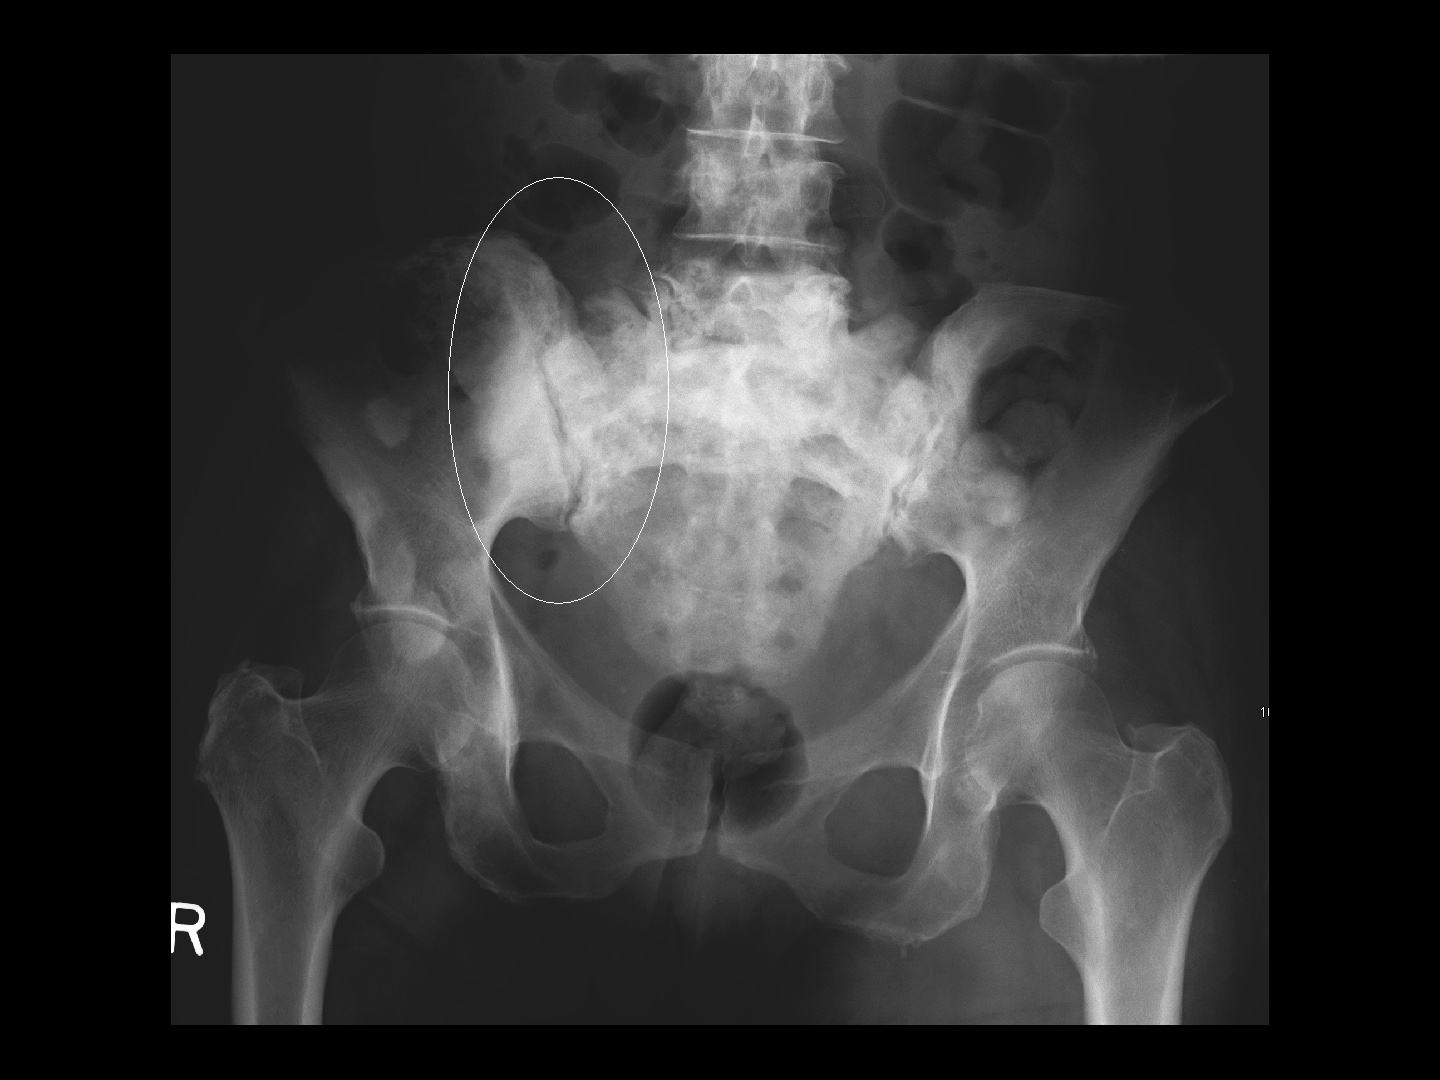

Hämatogene Fernmetastasen: Knochenmetastasen

Am meisten betroffen ist das Achsenskelett und der proximalen Abschnitt der Röhrenknochen. Symptom: Skelettschmerzen

CC BY-SA 3.0, James Heilman, eigene Arbeit, Knochenmetastasen im Becken,

Knochenmetastasen im Becken - CC BY-SA 3.0, James Heilman, eigene Arbeit, Knochenmetastasen im Becken,